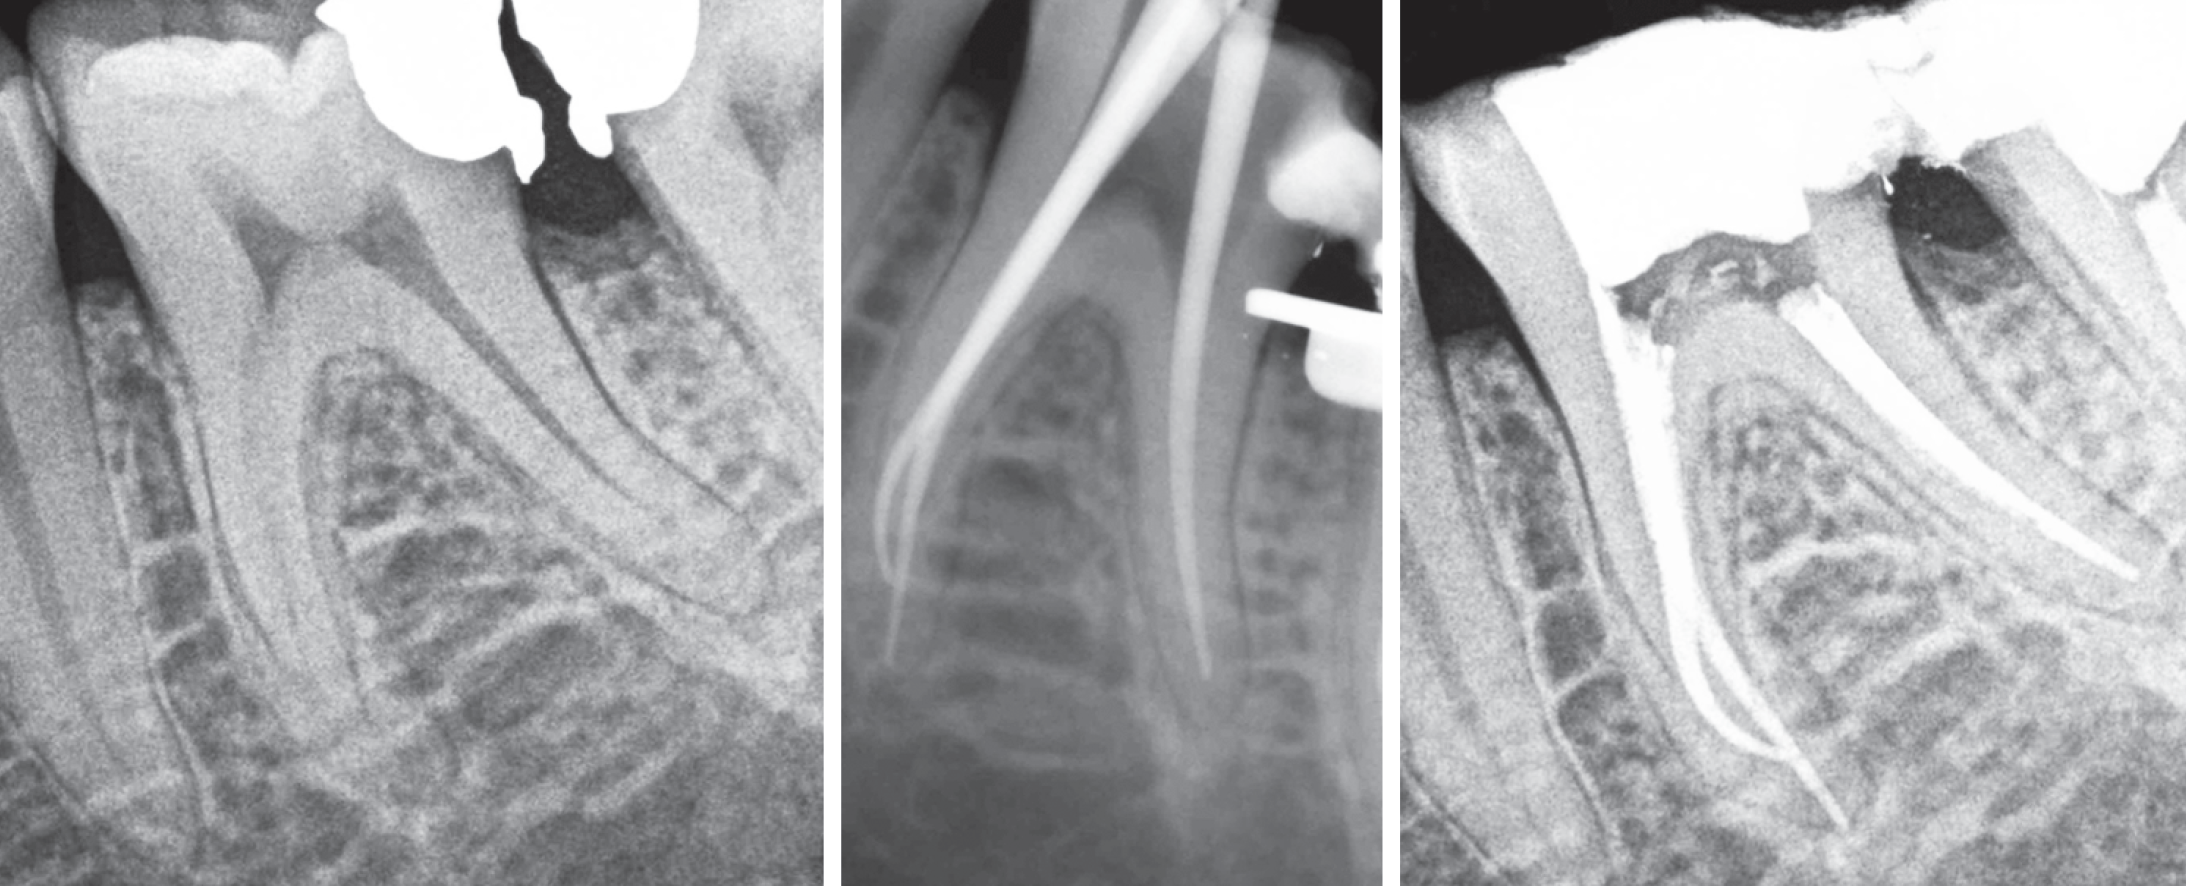

Case description: The operative technique started with canal scouting and determination of working length using a size 10 SS K-file. Then, a specific sequence was applied using the F1 20.06v Ni-Ti austenitic file (EdgeTaper) for the preparation of the coronal and middle parts of the canal. This step was followed by S2 20.04 and F120.06v martensitic Ni-Ti files (EdgeTaper Platinum) to enlarge the canal until the apex reached. No intracanal breakage of any instruments or deformation of flutes was recorded.

Conclusion: The present study describes a new HHT technique aiming at simplifying procedures and taking most of the different characteristics of the different heattreatment; the clinical cases seem to show its potentialities in terms of safety, speediness, effectiveness, and preservation of original anatomy.